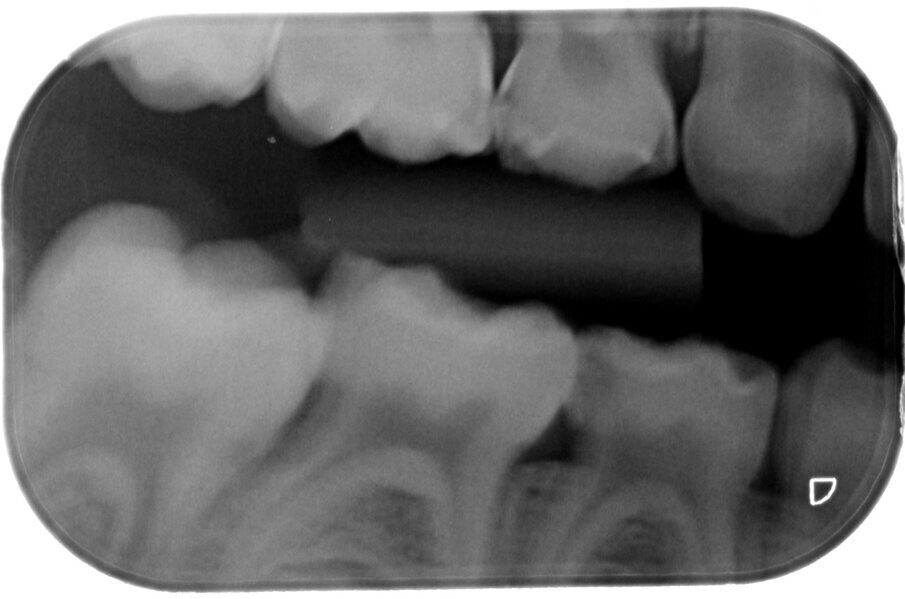

Zilverdiaminefluoride wordt sinds de jaren zestig van de vorige eeuw veelvuldig succesvol toegepast, zoals te lezen is in de reviews van Chu en Lo.1 Het bevat 44800 ppm fluoride, dus ongeveer de dubbele concentratie van de middelen die we gewend zijn zoals Duraphat en Enamelast, die 22600 ppm bevatten. Bovendien heeft het vrije zilverionen die een bactericide werking hebben (afbeelding 1-4).

Afbeelding 1. Casus 1: 18-12-19. Kiespijn dreigt. ZDF aanbrengen veroorzaakte minutenlang pijn.

Afbeelding 2. Casus 1: 13-03-20. Na 4 maanden zwart verkleurd en symptoomvrij met vitale pulpa.